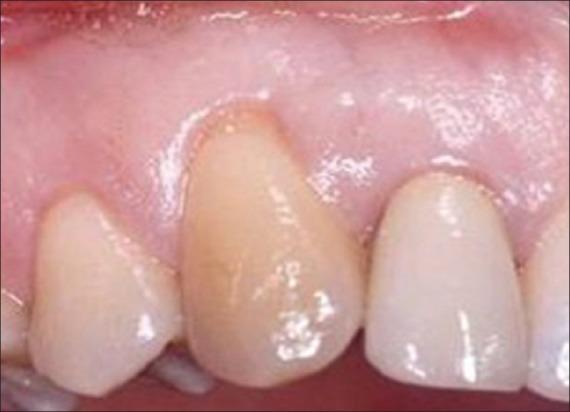

Gingival recession is a common occurrence and patients often report to dental clinic with associated problems such as root surface hypersensitivity, esthetic concerns, cervical root abrasions, and root caries that make it a concern for patients. Based upon the fact that gingival recession is an enigma for clinicians because of multitude of etiological factors and plethora of treatment modalities present for its treatment, a survey was conducted to assess knowledge as well as opinion about most common etiology, classification, and preferred treatment of gingival recession and to evaluate the interest and satisfaction of dentists in practicing periodontics.

牙龈退缩是一种常见情况,患者常因相关问题如牙根面过敏、美观问题、颈部牙根磨损和根龋等前往牙科诊所就诊,这使其成为患者关注的问题。鉴于牙龈退缩因多种病因和大量治疗方式而给临床医生带来难题,开展了一项调查,以评估关于牙龈退缩最常见病因、分类和首选治疗方法的知识及看法,并评估牙医对牙周病学实践的兴趣和满意度。